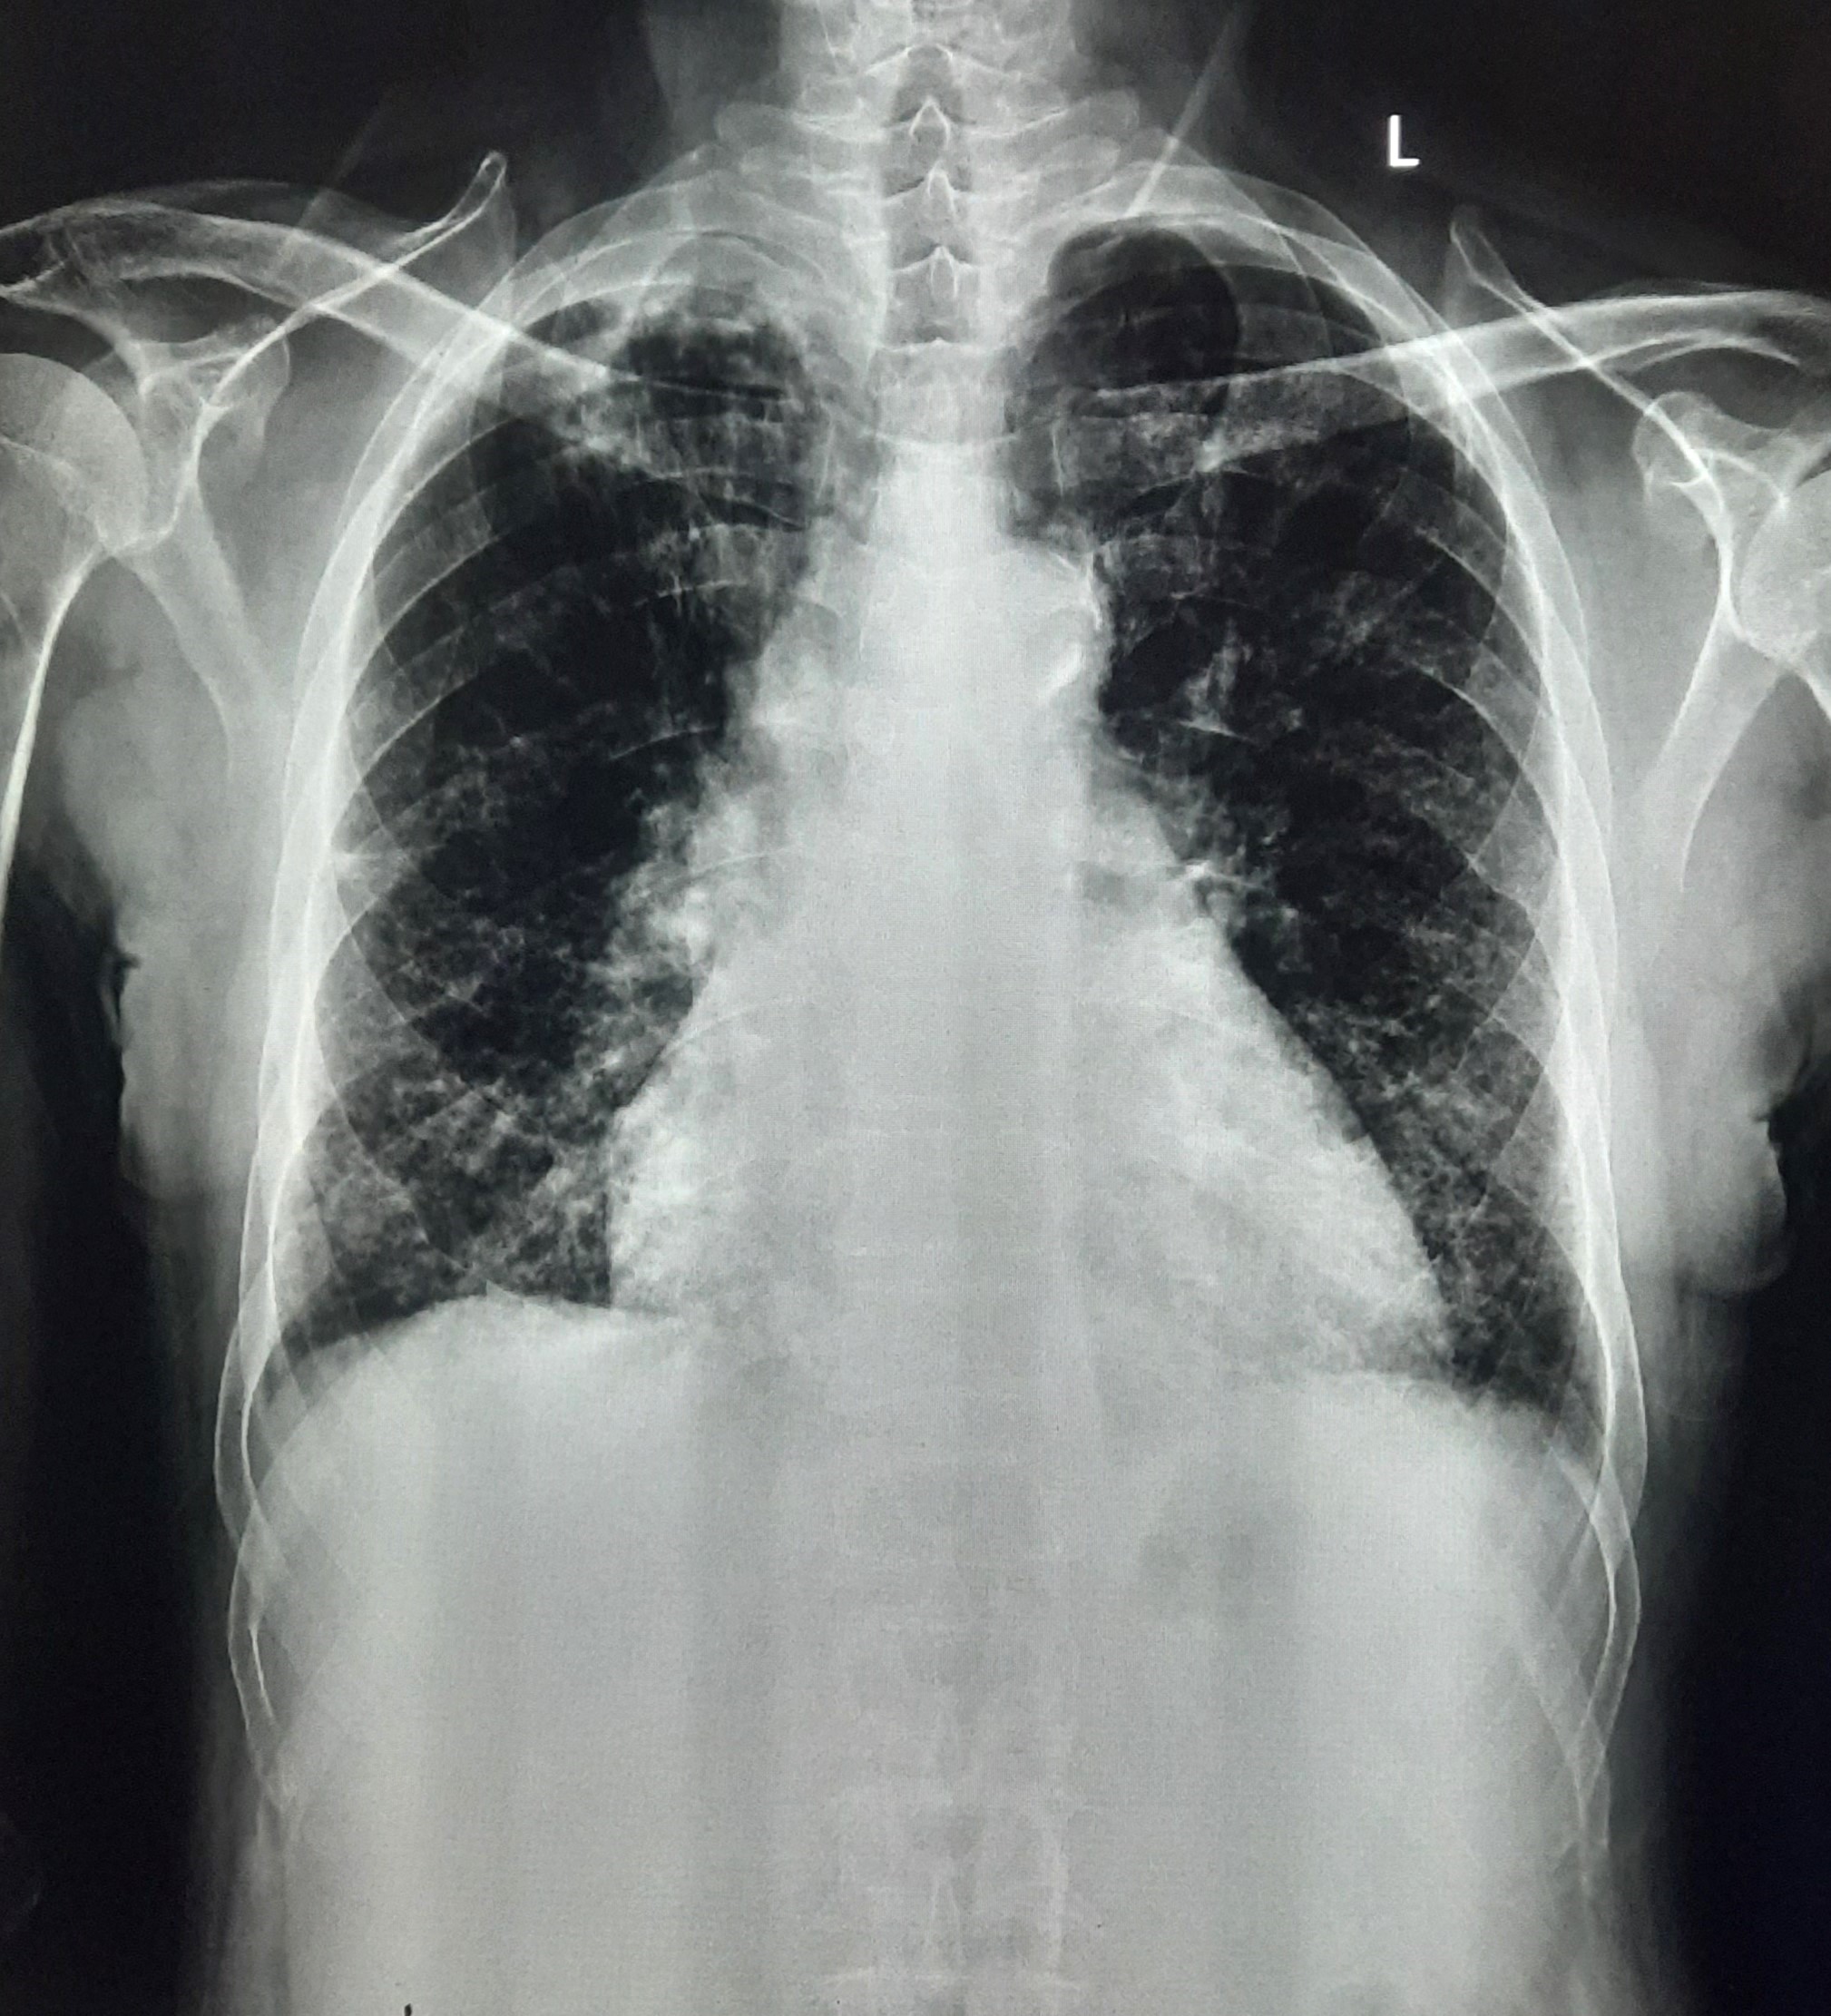

| 154 | IGGMC, Nagpur, Nagpur | P2 | 29-4318 | Manohar Jaiswal | Consent taken on Paper | 68 Yrs. |

Provisional Diag : ?

Final Diag : ? |

Special Normal (Cases with complaints or abnormality in x-ray) | Right Lung Apical Fibrosis Present With Bilateral | ? |